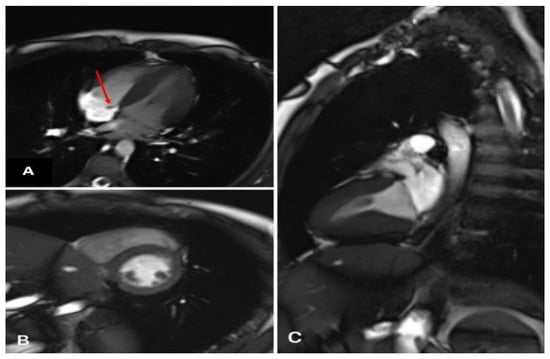

Figure 1.

Echocardiography (dynamics of thrombus regression). (A) Thrombus was in the septal leaflet of the tricuspid valve (red arrow) upon admission, size 16 × 6.5 mm. (B) Two weeks after the start of anticoagulant therapy. The red arrow indicates a thrombus with dimensions of 12.5 × 7 mm. (C) Lysis of a thrombus in the septal leaflet.

Applying echocardiography data, prolapse in the diastole cavity of the right ventricle was revealed. The projection of the tricuspid valve leaflets, a homogeneous formation with fuzzy contours, 16 × 6.5 mm in size, on a wide base were examined (Figure 1A).

The dimensions of the heart were not enlarged, and the contractility of the right and left ventricles were preserved. The condition was regarded as the course of infective endocarditis of an unspecified etiology with tricuspid valve damage.

During echocardiography, the formation of a tricuspid septal leaflet on a wide base, and a thrombus could not be ruled out. It was clearly visualized with even edges (12.5 × 7 mm in size) and a tricuspid septal leaflet was not floating. The biomechanics of the valve were not impacted. The dimensions of the heart chambers were normal and myocardial contractility was preserved; however, basal lower septal segment dyskinesia was detected (Figure 1B).

A formation with clear contours was determined. There were no signs of myocardial edema. On delayed post-contrast images, there was no distinct pathological accumulation of the contrast agent in the myocardium (Figure 2).

Figure 2.

Heart MRI with contrast. (A) Four-chamber plane (formation of a septal valve—red arrow). (B) Two-chamber plane along the short axis (normal). (C) Two-chamber plane along the long axis (norm).